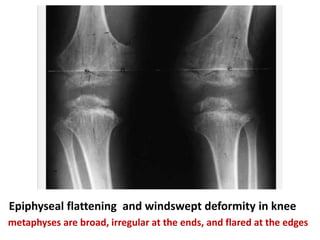

Deformation and delay in the ossification of the epiphyses

Epiphyseal flattening and windswept deformity in knee

metaphyses are broad, irregular at the ends, and flared at the edges